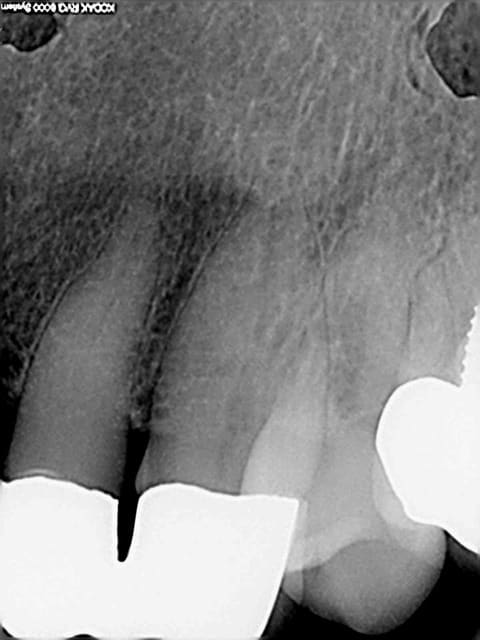

Je reçois ce matin ce mail plutôt désagréable, intitulé "votre devis hors norme", suite à une consultation en juillet pour un abcès sur la 12 (je joins les radios).

Le choix thérapeutique dépend de la balance bénéfice/risque. Pour moi la racine de la 12 n'est pas conservable (et donc le bridge non plus) car la racine est très courte et le tenon est très long. La résection apicale raccourcit encore la racine, et raccourcit d'autant la durée de vie de cette racine. J'ai donc écarté ce choix thérapeutique car il s'agissait pour moi de reculer pour mieux sauter. Mais peut-être me suis-je trompé, après tout je ne suis pas encore un chirurgien dentiste de renom. Seul le temps pourra dire si j'avais tord ou raison.

Sauf que la solution de la chir apicale n'existe pas dans ce cas là. Pour moi, la dent n'est pas conservable point. Car ratio couronne/racine de 3 pour 1 aggravé par une chir apicale, car pas 5 mm de gutta entre le tenon et l'apex, car gros risque de fracture de la racine.

Les deux seules solutions qui existent c'est la solution implantaire et la solution amovible avec ses crochets apparents, son décapsulage des dents voisines et autres joyeuseté iatrogènes...